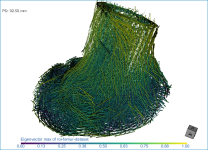

This section of the proximal femur tutorial describes how to compute high-resolution anisotropy maps in different orientations. You should note that when computing high-resolution maps, you should limit the volume of operation to regions that enclose only part of the region of interest. This can be done by creating a series of boxes that describe a particular orientation.

The images below (from left to right) correspond to XZ, XY, and oblique orientations. The computed vector fields are colored by magnitude.

High-definition vector field-based surface anisotropy maps